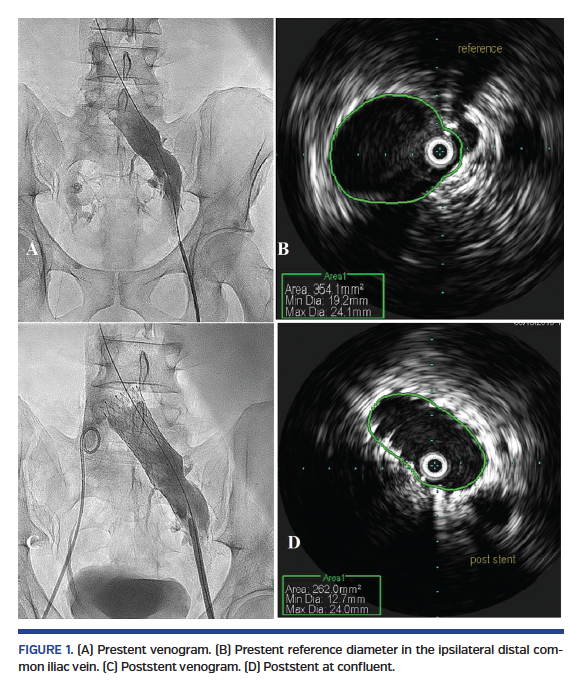

The patient was a 41-year-old male (body mass index, 25.6 kg/m2) who presented with postthrombotic syndrome of the left leg with swelling and discomfort and lower back pain. He was in clinical, etiologic, anatomic, and pathophysiologic (CEAP) class III. He had history of pulmonary embolism, was a smoker, and had history of hyperlipidemia. He was on dabigatran for history of antiphospholipid antibody. He could not take warfarin, rivaroxaban, or apixaban because of headaches. After discussion of alternatives, risks, and benefits, the patient elected to proceed with venography and IVUS of the left leg and stenting as needed. The patient underwent his procedure. Venography revealed left to right iliac vein collaterals. Prestenotic dilation of the left CIV was seen on both venography and IVUS (Figure 1). Pretreatment minimal luminal area (MLA) in the ipsilateral non-compressed segment of left CIV (reference) was 320 mm2. The theoretical stent diameter was approximately 20 mm. The Venovo 20 x 60 mm stent was selected. The MLA at the confluent was 110 mm2 and the percent stenosis was calculated at 65.6%. Significant dense fibrosis was seen by IVUS at the compression site. The lesion was predilated at 14 atm followed by stent deployment. The stent was deployed accurately at the confluent with mild protrusion into the IVC. Postdilation was carried on with a 16 mm balloon at 12 atm. The MLA post stenting was 250 mm2, which was markedly improved and over the goal of 200 mm2 for optimal flow. There were no complications during the procedure. Post procedure, the patient had some back discomfort — which was not unexpected — and was given pain medications and discharged home the next morning.